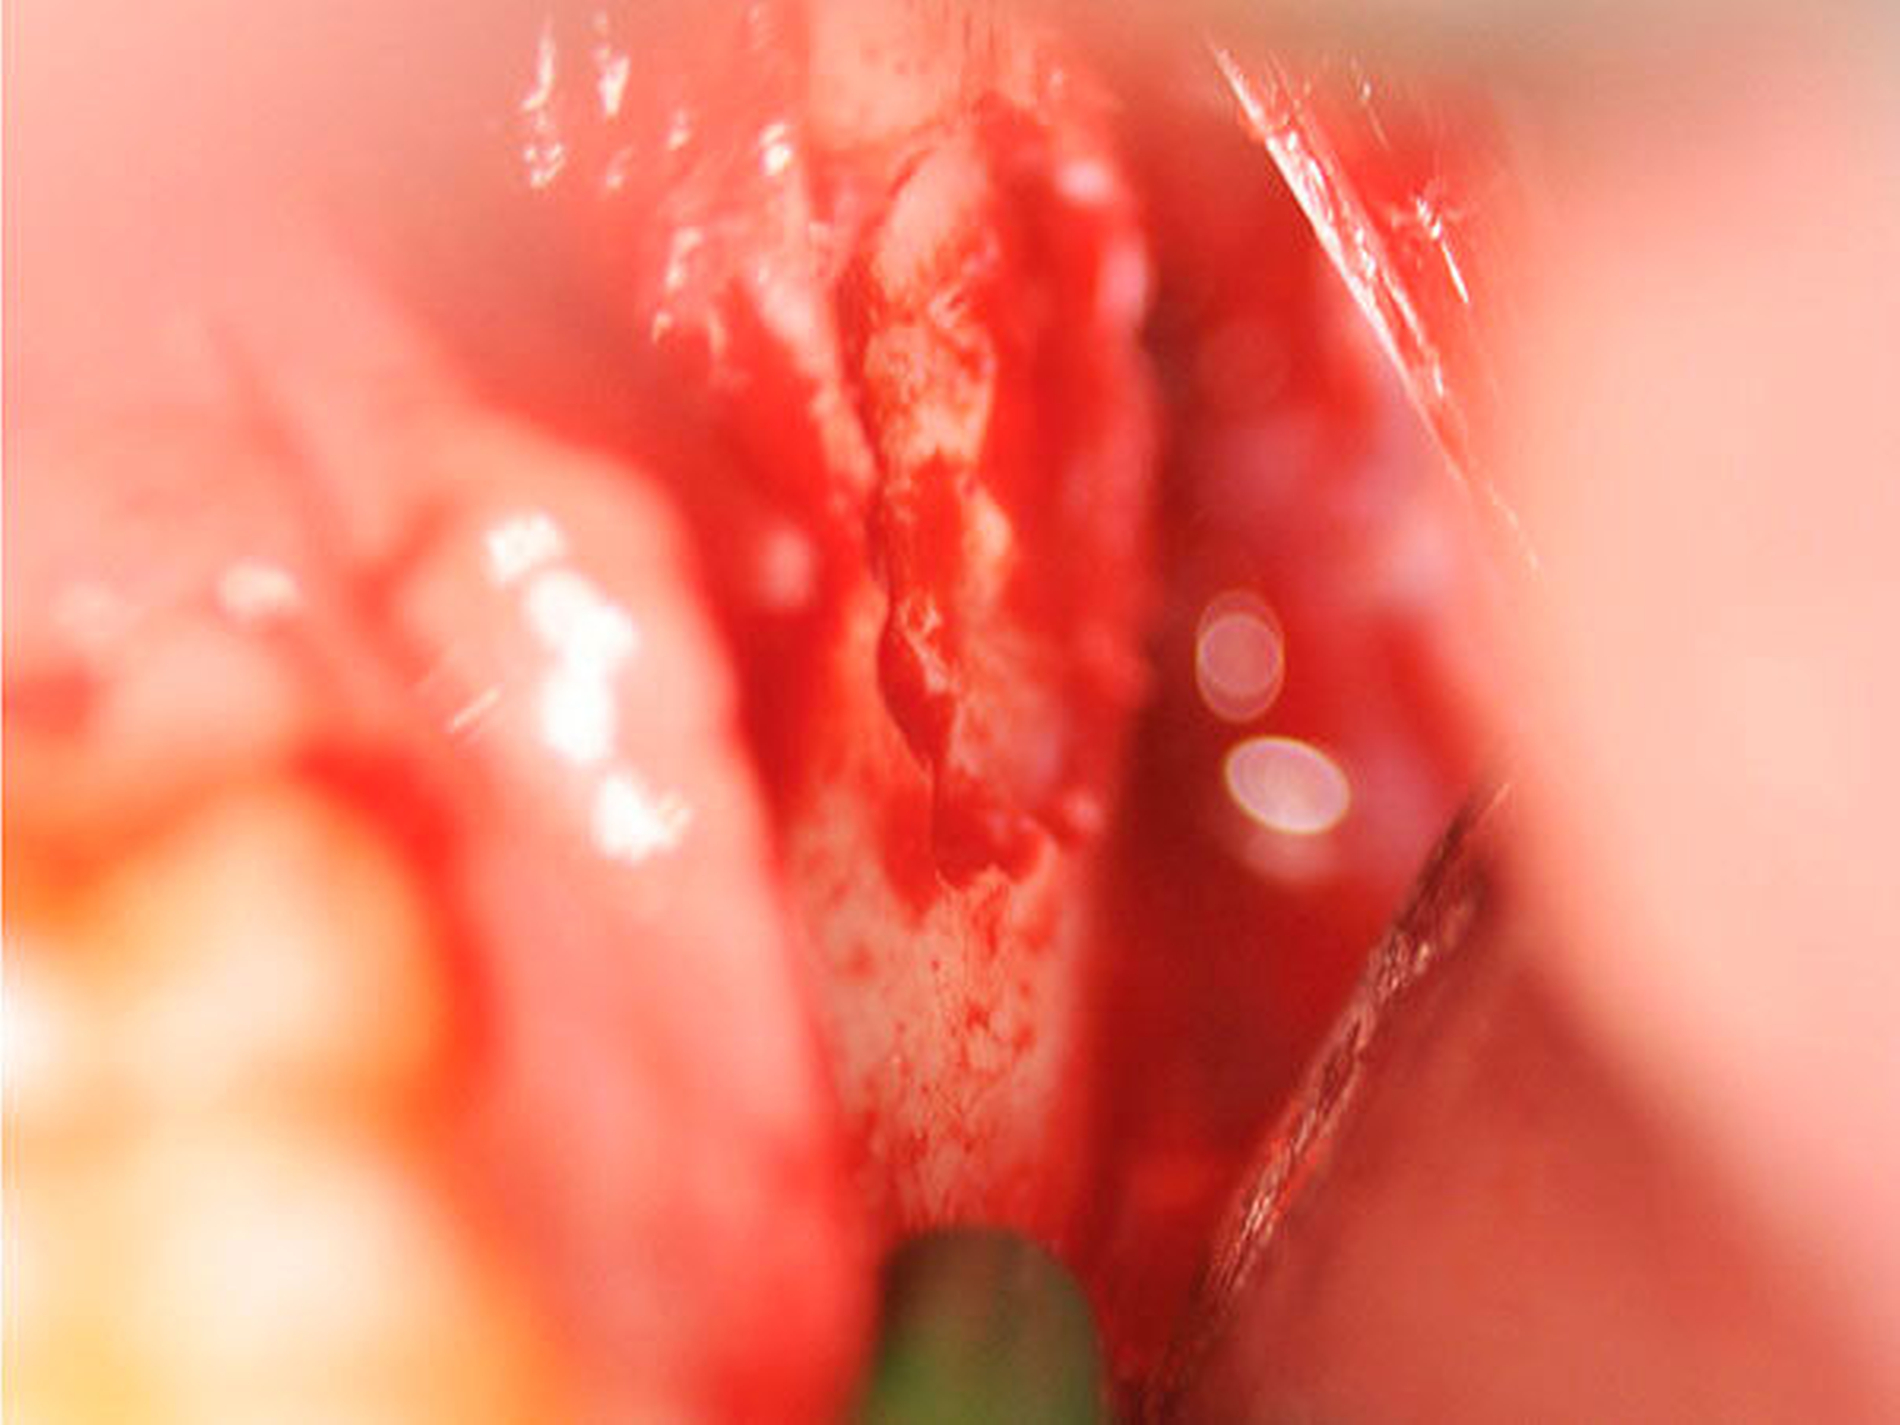

Im Lokalbefund zeigte sich eine stark druckdolente perimandibuläre Schwellung des linken Unterkiefers (Abbildung 2), wobei die junge Patientin aufgrund der Schmerzen ihren Speichel nicht mehr schlucken wollte. Zur Feststellung der Ausdehnung und Abgrenzung gegenüber Nachbarstrukturen erfolgte die weiterführende 3-D-Diagnostik mittels DVT (Abbildung 3). Aufgrund der klinisch ausgeprägten Beschwerdesymptomatik sowie radiologisch nicht eindeutigem Bild (follikuläre Zyste ausgehend von Zahn 38 beziehungsweise odontogene Keratozyste) erfolgten eine Probeexzision der Zystenwand sowie eine Erweiterung der Drainage in Intubationsnarkose. Der bereits vorhandene Schnitt wurde auf regio 35–37 vestibulär ausgeweitet und der subperiostale Knochen dargestellt.

Das Knochenfenster der regio 37/38 konnte ohne Beschädigung der Zystenwand abgehoben werden (Abbildung 4). Nach der Biopsie-Entnahme entleerte sich ein grießiges Material aus der Zyste. Es erfolgte eine ausgiebige Spülung, dann die Einlage einer neuen Drainage sowie eine postoperative i.v.-antibiotische Therapie mittels Ampicillin/Sulbactam (Unacid®).